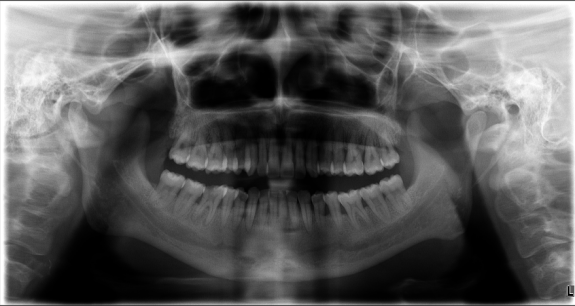

通过对患者进行口腔全景片检查及全身系统性疾病(血源性疾病、肝功能异常及糖尿病病史等)排除后,口腔科诊断为:慢性牙周炎(中度),并制定针对性的治疗计划:序列牙周治疗。通过2次完善超声龈上洁治+超声、手工龈下刮治+手工根面平整等系列牙周基础治疗,1个月后患者的牙龈健康得到明显改善,牙龈不再出血,口臭也明显减轻。